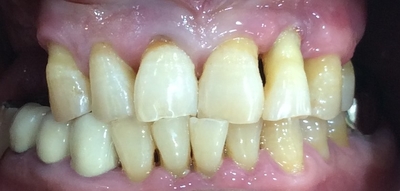

환자분 처음 오셨을 때 사진입니다.

앞니 4개가 많이 흔들려서 치과를 찾게 되셨습니다.

그리고 기존 틀니가 많이 불편하셨죠.

임플란트를 권해드렸으나

환자분 사정으로 앞에 많이 흔들리는 치아 4개는 뽑고 송곳니를 건 브릿지와

그 브릿지에 고리를 걸어 틀니를 하기로

환자분과 상의 후 결정하였습니다.